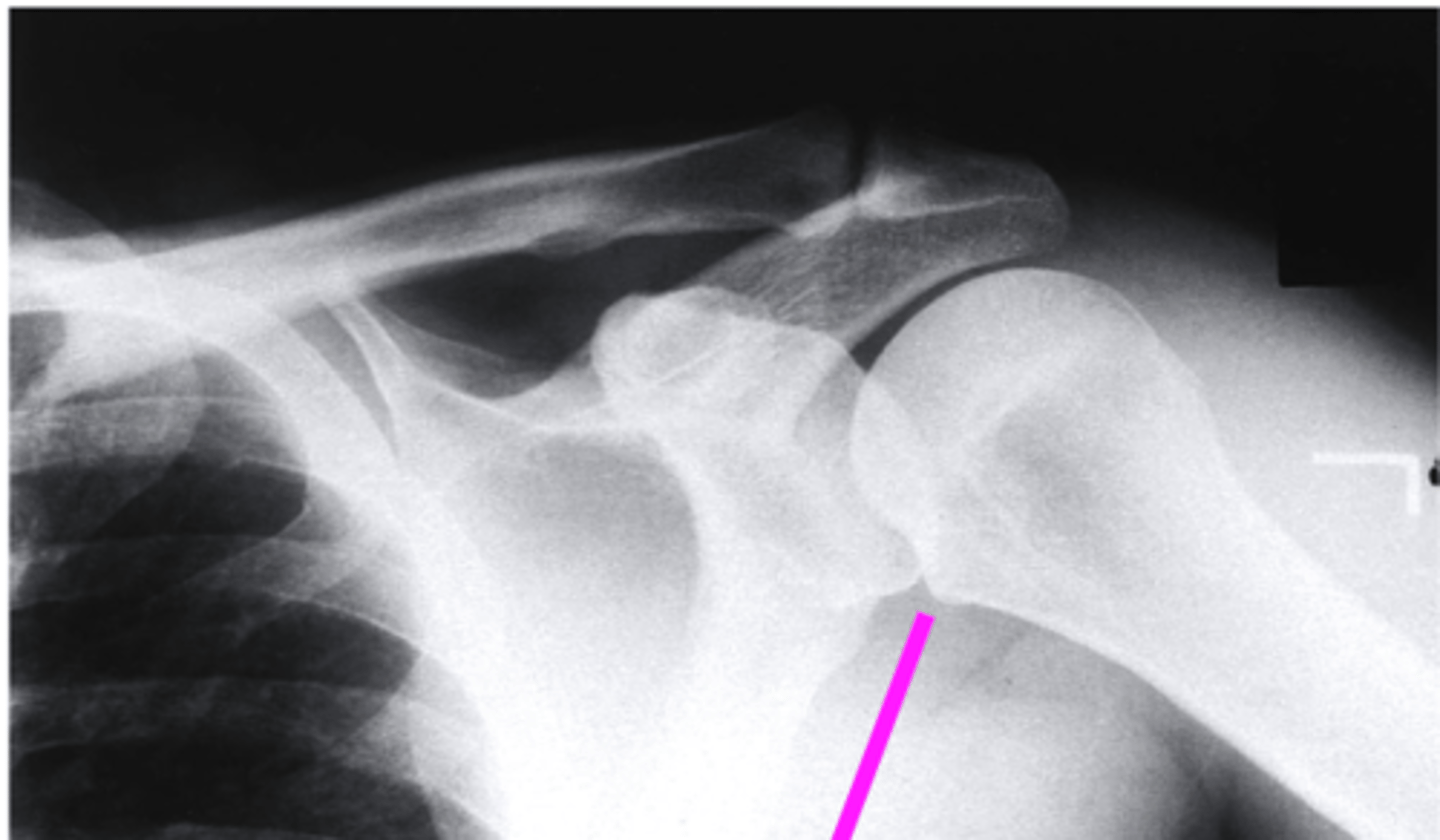

AP + IR

what view is this?

clavicle

what does the pink line point to?

spine of scapula

coracoid process

glenoid fossa of scapula

AC joint

acromion

Humeral Head

lesser tubercle